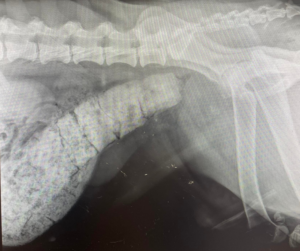

Constipația la câini

Constipația este o problemă digestivă frecvent întâlnită la câini, caracterizată prin eliminarea dificilă, dureroasă și [...]

Constipația la câini: O problemă frecventă

Constipația la câini este o afecțiune des întâlnită, dar adesea subestimată de proprietarii [...]